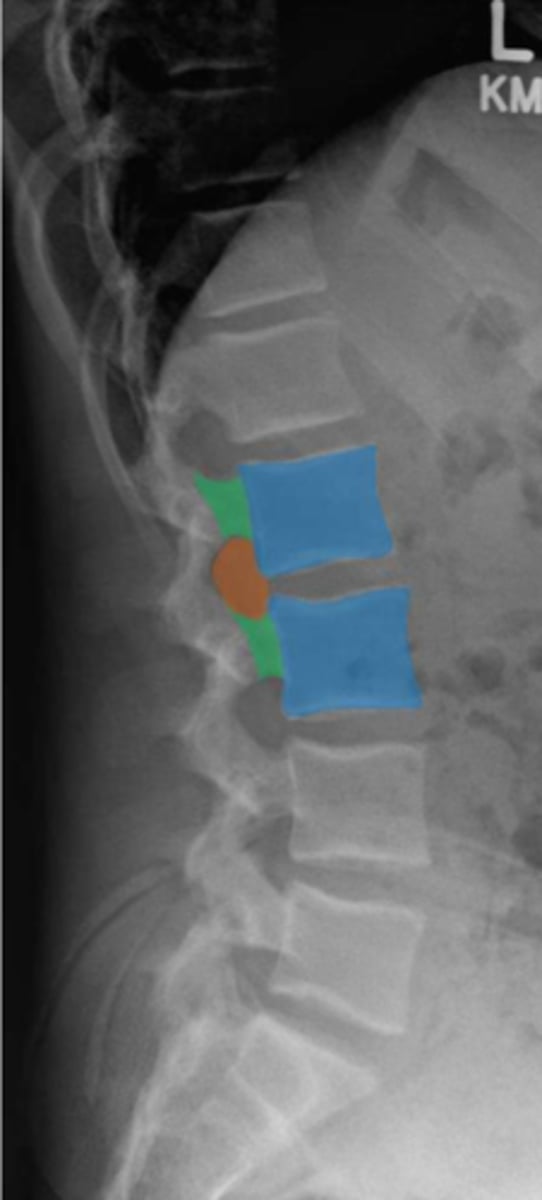

lumbar

What vertebrae is being examined?

lumbar vertebral body

Identify the blue structure

pedicles

Identify the green structure

transverse processes

Identify the purple structure

spinous processes

Identify the yellow structure

joint space between superior and inferior articulating facets

Identify the red line

intervertebral foramen

Identify the orange structure

pedicles

Identify the green structure

spondylolysis

pars interarticularis

oblique view

What condition is being examined for in this radiograph?

What structure is it looking for?

What view is this radiograph in?